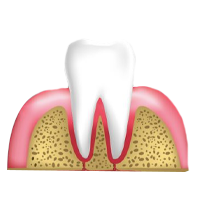

perio1

Diente y encias sanos